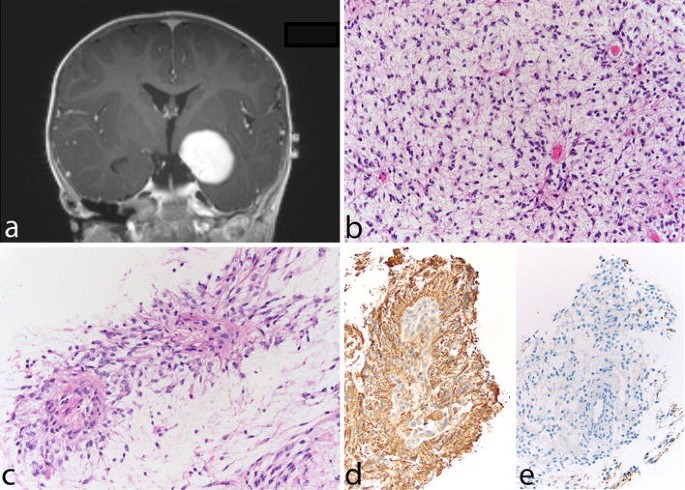

Pilocytic astrocytoma of the optic nerve. Bilateral fusiform enlargement of the optic nerve is virtually diagnostic of neurofibromatosis type 1 (a). The tumor typically extends into the leptomeningeal space, expanding the dural sheath and compressing the remaining optic nerve proper, which is atrophic (b). A complete cross section of the optic nerve is shown in the inset. The tumor has classic PA features with a densely fibrillated appearance and numerous Rosenthal fibers (c). The interface between the optic nerve and the tumor is shown in (d), while the subdural region shows meningothelial hyperplasia, at times, with scant psammoma bodies (e)

Histopathologically, PA is a tumor of low to moderate cellularity with compact, densely fibrillated areas rich in Rosenthal fibers, consisting of cells with long bipolar (hair-like) processes and elongated cytologically bland nuclei (Fig. 2c), as well as loosely textured areas, composed of multipolar cells (protoplasmic astrocyte-like), with bland, round-to-oval nuclei, and multiple, relatively short cytoplasmic extensions. These areas have varying degrees of mucoid background material with micro-cyst development being common, as are also eosinophilic granular bodies or hyaline droplets. The bipolar tumor cells are generally strongly GFAP immunoreactive, while the protoplasmic astrocyte-like tumor cells are less so. In some cases, areas morphologically similar to oligodendrogliomas may be found, but only rarely is the oligodendroglial-like component predominant (see “Differential diagnostic issues”). Cells with pleomorphic nuclei, often multinucleated, may also occur and generally are found in the loose microcystic regions. Rare mitoses are acceptable, but any notable mitotic activity should warrant the consideration of other glioma diagnoses. Ki67/MIB-1 indices of up to 4 % are common. Microvascular proliferation, resulting in relatively thick-walled, hyalinized, and/or glomeruloid vessels, is often seen, and infarct-like necrosis can occur in some cases (no pseudopalisading) [24]. While these findings are all compatible with a diagnosis of PA, they sometimes make the distinction from other gliomas difficult, particularly when examining small biopsies. While macroscopically appearing relatively well-defined, microscopically, varying degrees of invasion into the adjacent brain are observed [26]. Rare cerebellar tumors show a diffuse pattern of growth, and molecular analysis may be of some help in identifying these tumors as PAs (see below). Consequently, both normal astrocytes and neurons may become trapped in the tumor tissue. Microscopic infiltration of the leptomeninges frequently occurs, especially in the cerebellum and optic nerve tumors, and is not an ominous finding. Today, it is rare to see surgical resection specimens from optic nerve gliomas in NF1 patients, given the often benign and indolent natural history of these tumors, which may, at times, regress. On cross section, the optic nerve outline is often visible near the center of the specimen, while the tumor characteristically grows in the subarachnoid space between the nerve and the dural sheath that is markedly expanded (Fig. 2b–d). Meningothelial hyperplasia may occur and represent a potential pitfall in the differential diagnosis between optic nerve PA and optic nerve meningioma when only a small and superficial biopsy is obtained (Fig. 2e).

Pilomyxoid astrocytoma. A 13-month-old boy presented with a relatively circumscribed, strongly enhancing left medial temporal lobe mass (a). The tumor shows a monomorphous cell population in a loosely arranged myxoid background (b). Tumor cells with angiocentric arrangement and formation of pseudopapillary structures is typical (c). GFAP is typically positive in tumor cells (d), and immunocytochemistry for neurofilaments is negative, the tumor being generally relatively solid and devoid of axons (e)